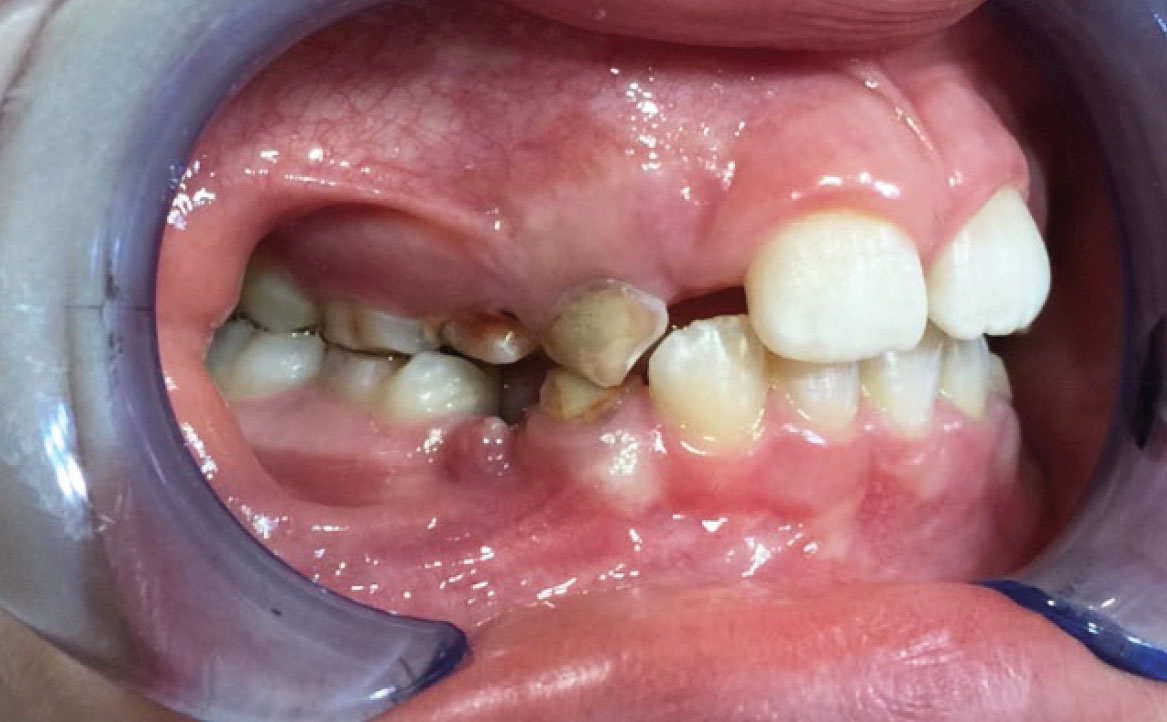

Dall’esame obiettivo intra orale si osservava una seconda classe canina destra e sinistra, una seconda classe molare destra e sinistra, e un diametro inter-canino e inter-molare ridotto sia in riferimento al mascellare superiore sia al mascellare inferiore (fig. 3A-3E).

Clinical examination revealed high caries risk, poor oral hygiene, and constricted upper and lower arches.